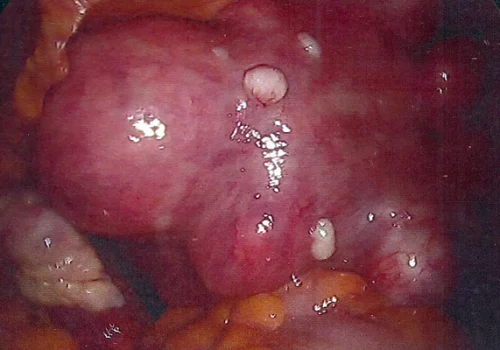

She had a large multi-fibroid uterus.

She subsequently underwent Total Laparoscopic Hysterectomy and removal of both Fallopian Tubes and Ovaries. The uterus weighed 670g.